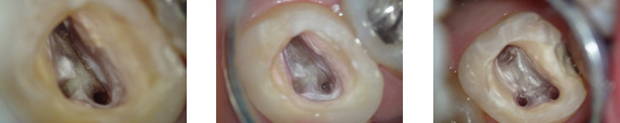

根管治療は、歯の内部にある細い管から感染物質を取り除く非常に繊細な治療です。従来の治療では、肉眼での確認に頼ることが一般的でしたが、マイクロスコープの導入により歯の内部を大きく拡大して観察できるようになり、これまで発見が難しかった細かな管や隠れた感染部位をしっかりと確認しながら治療を進めることが可能です。

マイクロスコープを用いることで、感染物質の取り残しを防ぎ、歯の保存率を向上させることが期待できます。